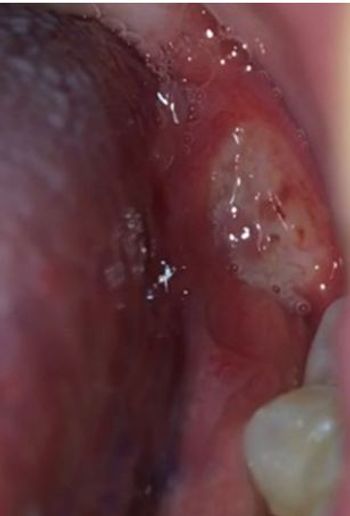

A 32-year-old man visits the ED for an oral canker sore that should have run its course but is getting worse. What one question should you ask?